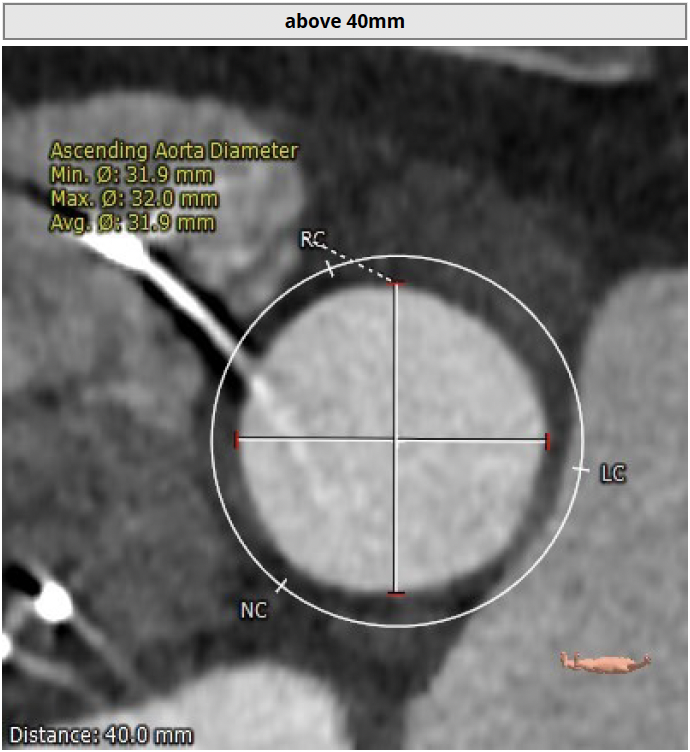

升主动脉

平均直径:31.9mm